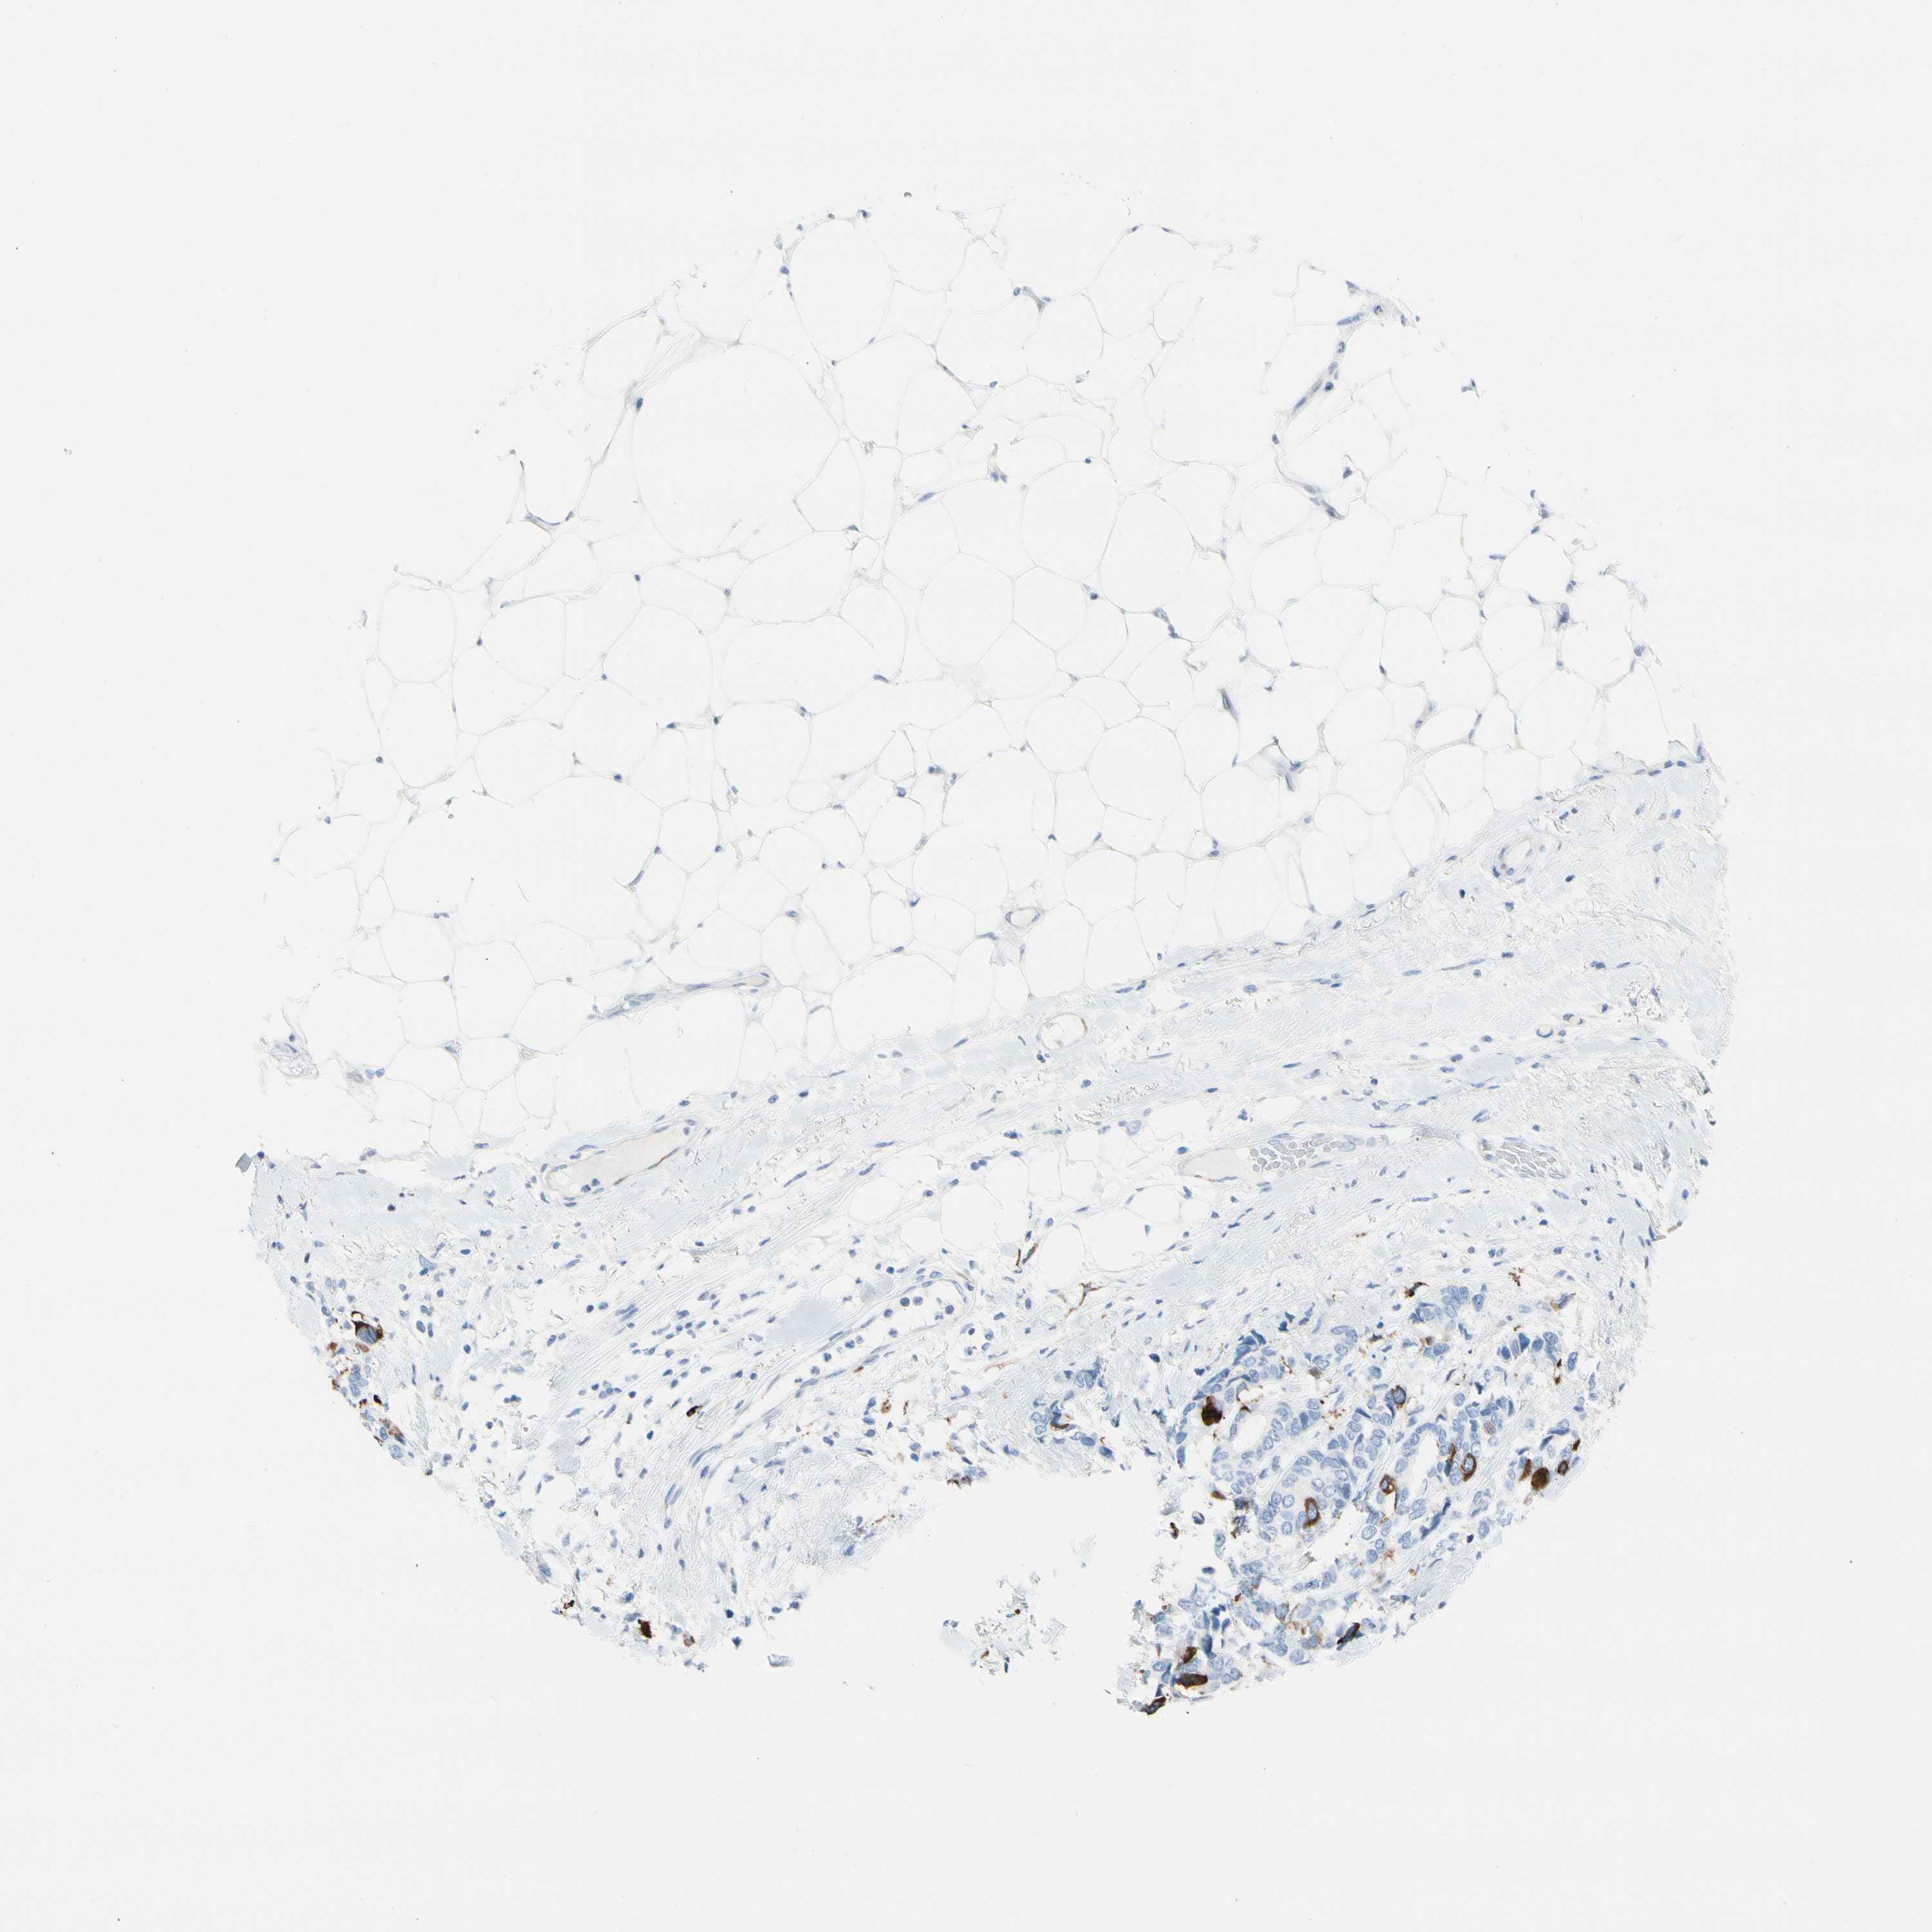

CANCER BREAST CANCER Show tissue menu

BRCA TCGA BRCA VALIDATION PROTEIN EXPRESSION